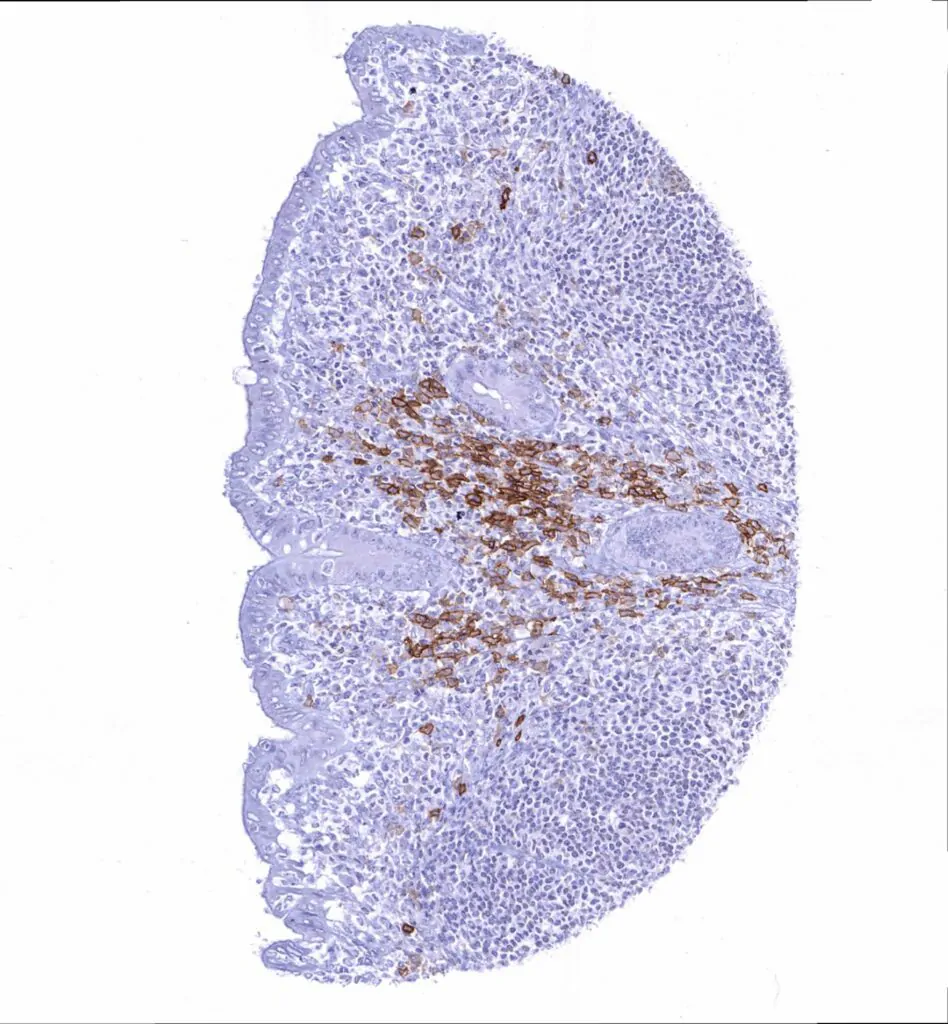

Tonsil – Distinct CD38 staining of a subset of lympho– histiocytic cells. CD38 staining is particularly prominent in cells (plasma cells_) located near the tonsil crypts

Tonsil – Distinct CD38 staining of asubset of lympho– histiocytic cells. CD38 staining is particularly prominent in cells (plasma cells_) located near the tonsil crypts